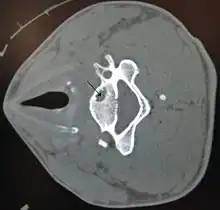

A bone cyst in the vertebra of the neck as seen on CT

On CT scans, bone cysts that have a radiodensity of 20 Hounsfield units (HU) or less, and are osteolytic, tend to be aneurysmal bone cysts.[1]

In contrast, intraosseous lipomas have a lower radiodensity of -40 to -60 HU.[2]